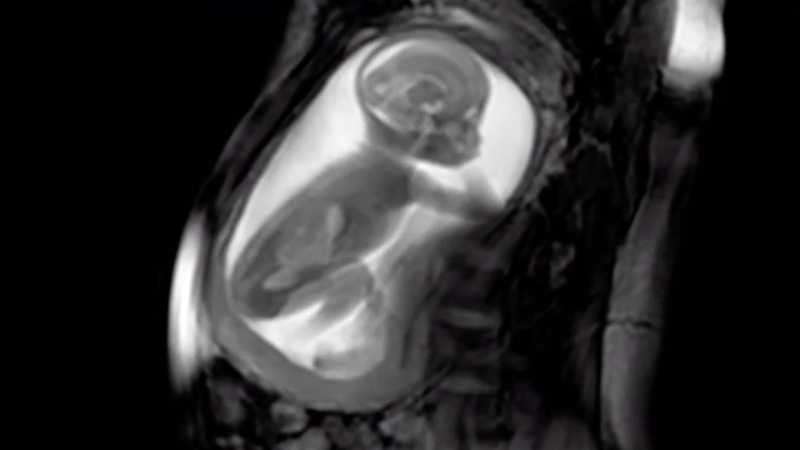

French Evangelicals Decry ‘Fatherless Assisted Reproduction’ That Turns Children Into ‘Products’

(Evangelical Focus) — France will approve a new bioethics law later this year which is expected to shape the future relationship between technology and human life. It is with this horizon in mind that the National Ethics Advisory Committee (CCNE